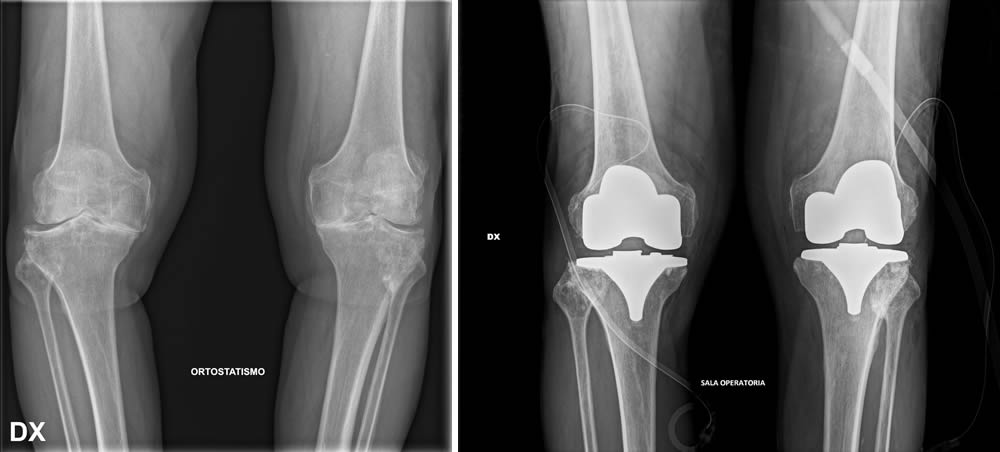

Per formulare una diagnosi corretta e ottenere un quadro clinico completo del paziente, è fondamentale eseguire una radiografia (RX) del bacino o bilaterale ginocchio in carico ovvero in piedi.

Prima e dopo l'intervento

Quando si prende in considerazione la protesi al ginocchio, si aprono diverse possibilità di intervento. È possibile optare per soluzioni mini-invasive che prevedono l'inserimento di protesi monocompartimentali, adatte a sostituire solo una parte dell'articolazione, oppure per protesi parziali o totali, in base alle esigenze e alla gravità della situazione. La scelta dell’intervento viene valutata attentamente dal chirurgo, mirando sempre a garantire il miglior recupero funzionale possibile.